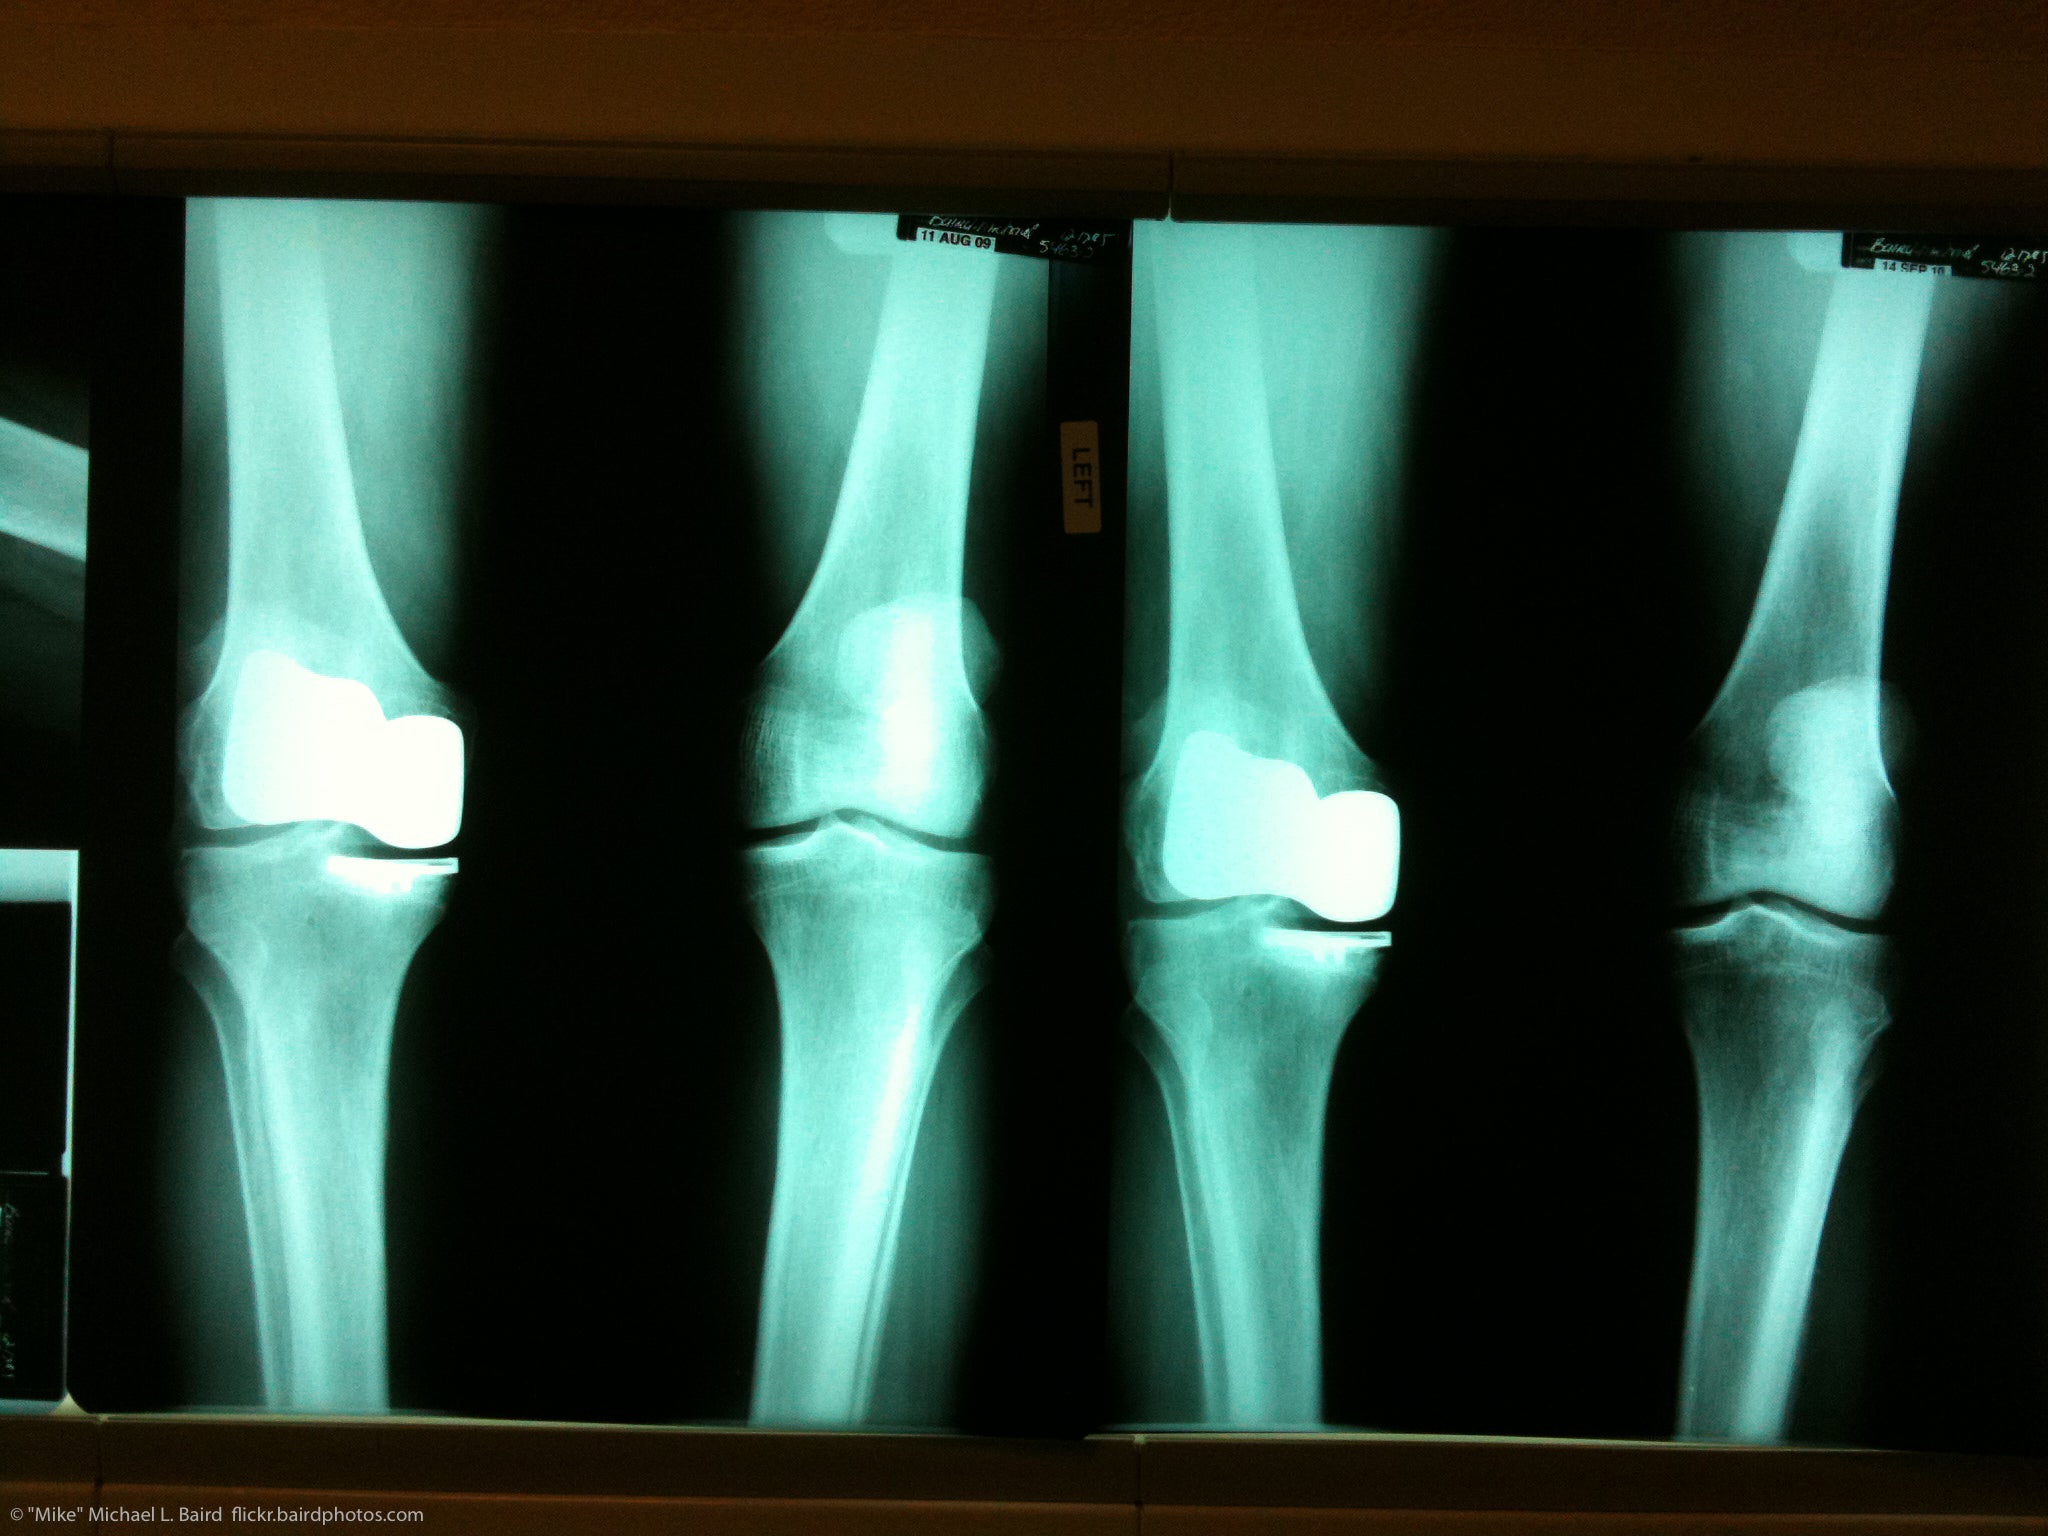

Over 700,000 knee replacements are done annually in the US. We speak with an orthopedic surgeon about advances in knee replacement, who is a candidate for knee replacement and what patients can expect as they recover.